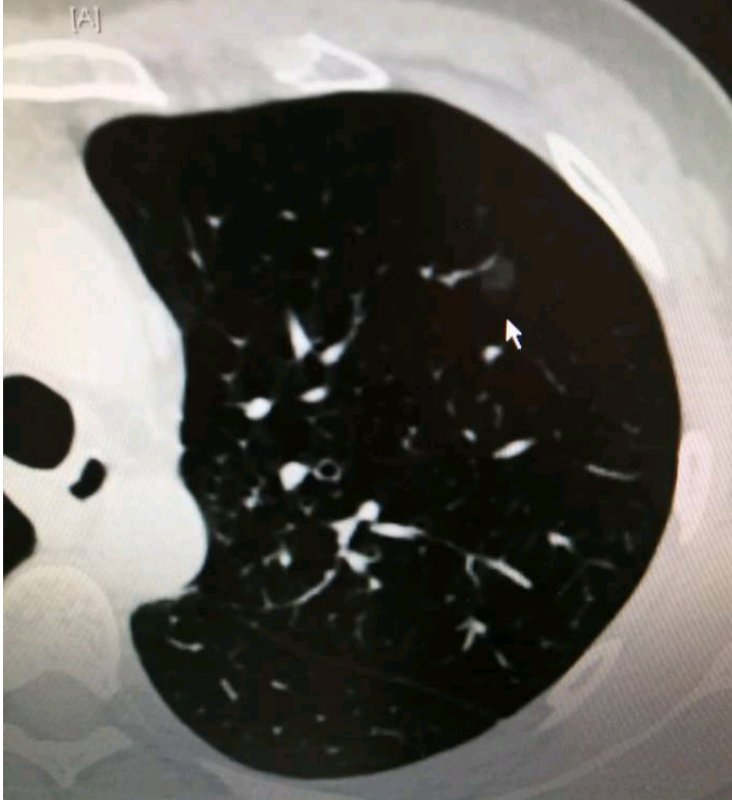

2010年时,吴先生在一次偶然的体检中发现自己左肺上有两个磨玻璃结节,去陆军军医大学新桥医院胸外科复诊时碰到了姚珂教授团队,姚教授仔细看过检查结果后发现他的两个结节位置都比较深,可能一般的楔形手术无法将结节切除干净,只能进行肺叶手术,考虑到结节比较小且表现都十分良好,恶变的概率很小,便建议他先随访一段时间。“那个时候我虽然很害怕,但是姚教授仔细帮我分析了,这两个结节如果要做手术的话就得做肺叶手术,一个人总的就只有5片肺叶,切掉一整片对后面的生活多多少少总会有些影响,他认为我还年轻并且结节恶变的概率几乎为零,所以让我先随访,如果结节有变化了再做手术也不迟。我想了很久,觉得姚教授说的有道理,毕竟那个时候我才三十多岁,家里很多苦活累活都需要我,所以我就听大夫的话,根据医嘱进行随访,谁知道竟然随访了九年,这对我的身体和精神来说都是一场持久战,还好今年终于把这个麻烦解决掉了。”说到这个,吴先生不禁满面笑容。

“这个患者,我印象很深,每年见一次都算是老熟人了”,一说到吴先生,姚教授立马就有印象:“在临床工作中我们碰到过很多磨玻璃结节患者,他们大多分为三类,第一类患者对磨玻璃结节一知半解,知道这种结节恶变概率高,发现结节后心理压力太大,吃不香睡不着,甚至会影响正常生活,这类患者不管结节的大小或具体表现如何都会强烈要求进行手术,不把结节切掉基本没法正常生活;第二类患者则完全相反,听到医生说磨玻璃结节惰性生长,并且结节表现良好建议随访时大多不会太放在心上,最开始一两年还能定期来医院随访检查,如果没啥变化则会将其抛诸脑后,等到后面出现症状再就诊时结节多已发展到中晚期。这两种患者在临床工作中是最常见的,但二者的心态都太极端,均不可取。吴先生这种情况则属于第三类患者,依从性好,医生解释后能放下大部分的心理负担,但又能谨记医嘱坚持随访,结节一旦发生变化就能及时手术,所以结节就算有所发展也多在肺癌早期,这类患者的预后一般都比较好。吴先生的两个结节都是IA期腺泡型肺腺癌,做完手术都不用再做辅助放化疗,治愈率非常高。”